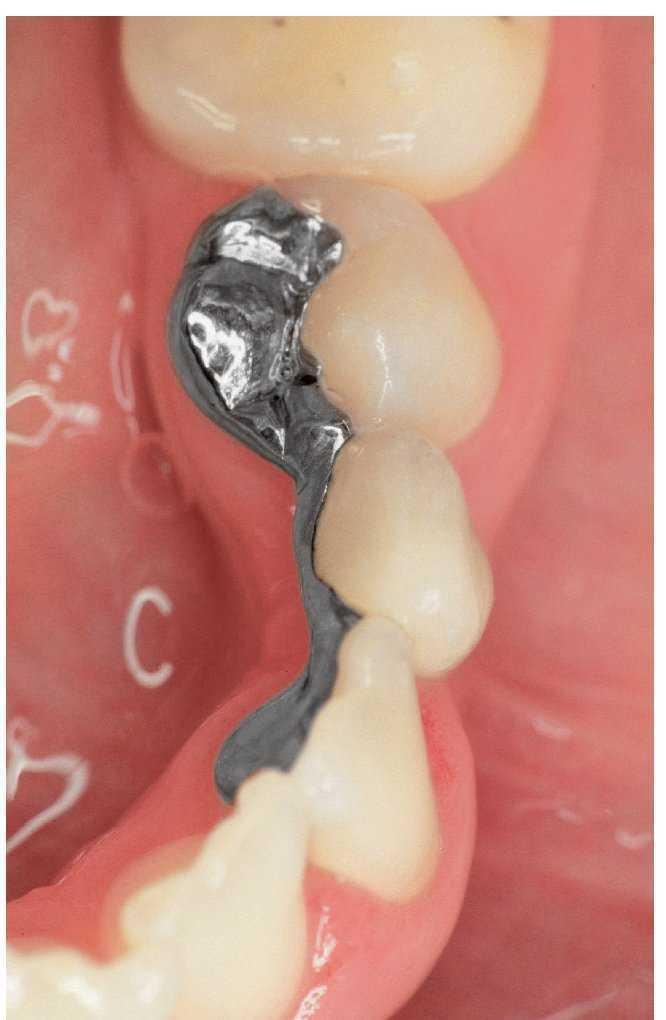

Figura 5a. Ausencia del diente 36, dientes adyacentes destruidos por caries.

Figura 5b. Reconstrucción de los muñones después de la extrusión ortodóncica mediante imanes de los dientes pilares18.

Figura 5c. Puente de metal cerámica que sustituye al diente 36.